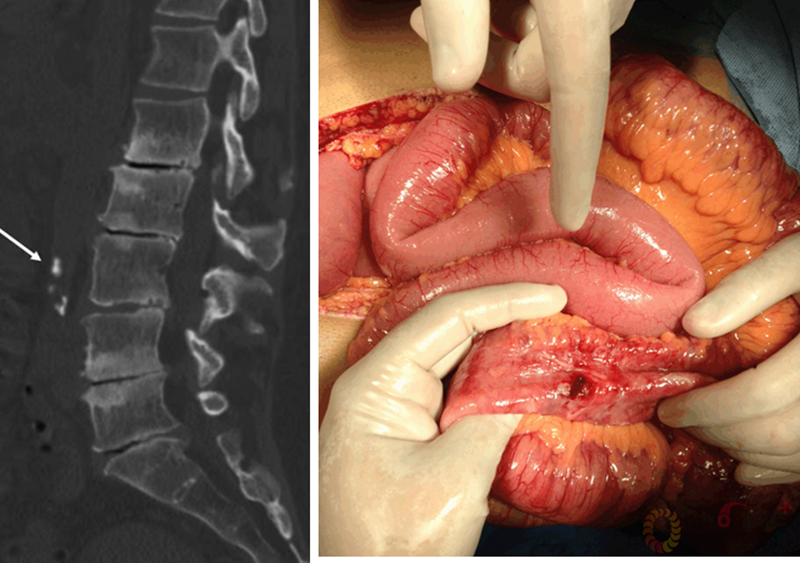

陆军总医院、全军骨科研究所李放教授分析了国内外相关研究,并结合临床经验得出结论:开放手术能够获得更好的矫形和减压效果;微创技术作为脊柱医生手中的新武器,对于一部分畸形较轻的病例,微创技术可以发挥其优势,但要严防特殊并发症;对于畸形严重的病例,微创手术处理存在困难,可谓开放能及微创所不及。他认为,开放和微创技术应该有机结合,重要的是如何去选择适应证,对不同的病例制订个体化方案。